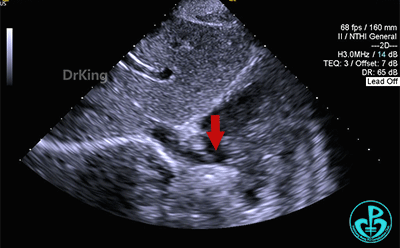

房间隔中部有回声中断,测ASD大小:8×8×9mm,CDFI探及左向右分流,距主动脉根部0mm,距二尖瓣环10mm,距房顶14mm,距上腔静脉13mm,距下腔静脉11mm。

心脏彩超提示:先天性心脏病:房间隔缺(继发孔型)。右室稍增大。左心室收缩及舒张功能正常。右心室收缩功能正常。下腔静脉瓣冗长。